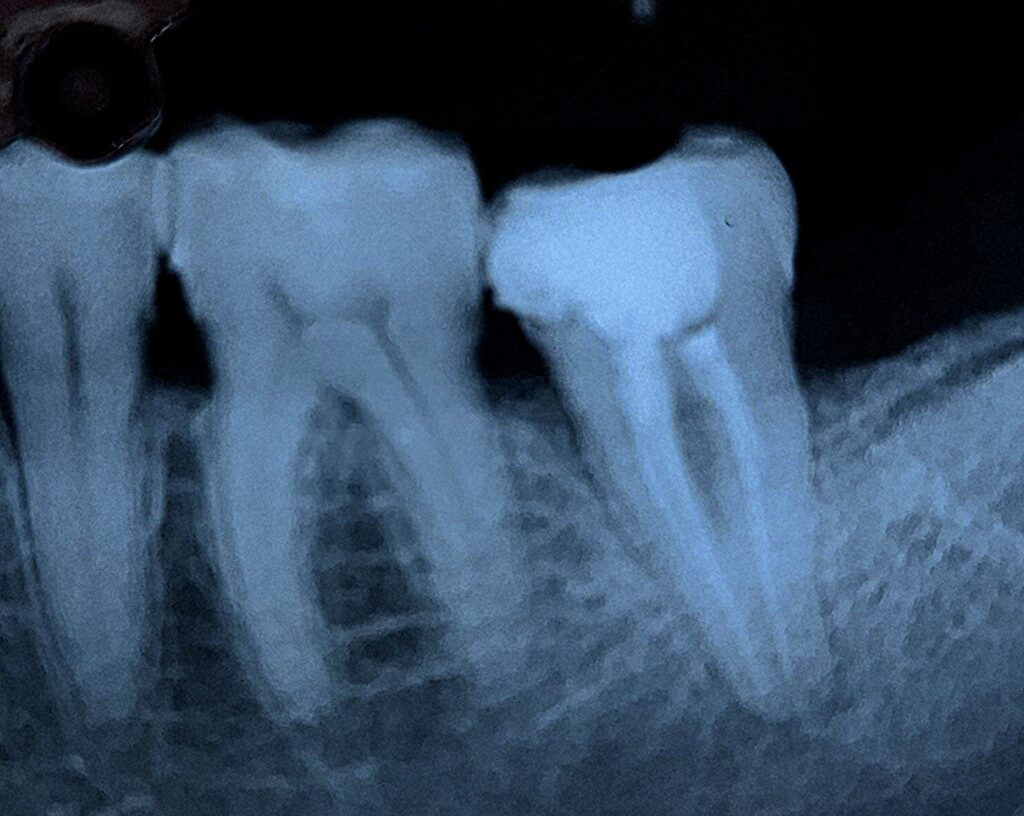

Veja alguns de meus casos